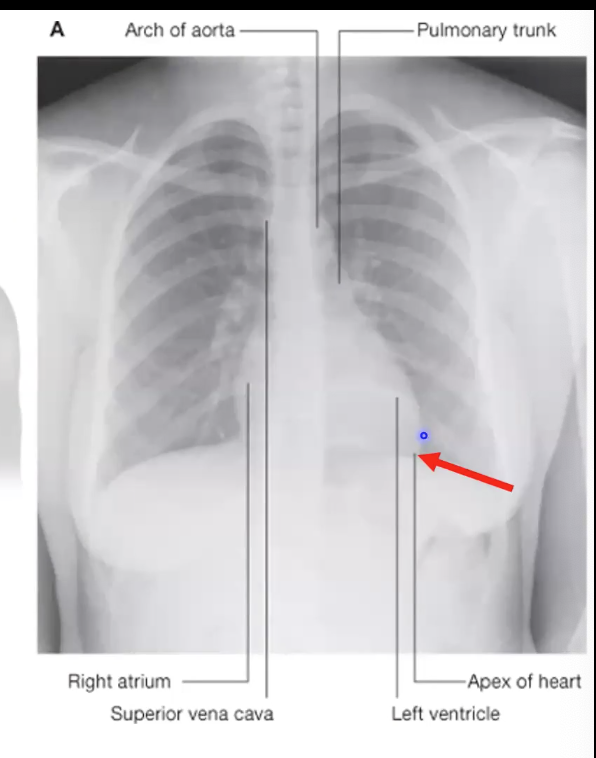

Identify the indicated features of the heart